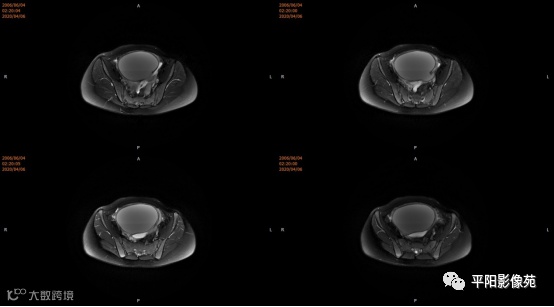

宫颈缺如、阴道闭锁

阴道闭锁

(1) 阴道闭锁I型:对应AFS系统中的阴道下段闭锁,阴道上段及子宫发育正常,内膜功能好

(2) 阴道闭锁II型:对应AFS系统重的阴道完全闭锁,常合并子宫颈闭锁,子宫体发育正常或有畸形,子宫内膜功能稍差

4.MRI检查 对软组织分辨率好,能够清晰区分子宫及阴道,对子宫内膜、结合带、肌层可清晰分辨;能明确子宫、宫颈、阴道结构异常的部位、范围、性质等。宫腔内经血潴留时,宫腔内见短T1长T2信号。